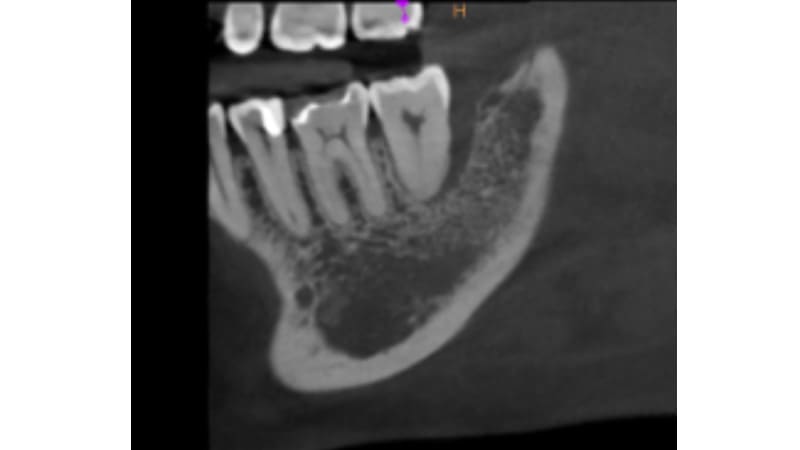

症例③:右下の奥歯に違和感がある

| 治療科目 | 歯周組織再生療法(エムドゲイン使用) |

|---|---|

| 主訴 | 右下の奥歯に違和感がある |

| 治療期間 | 1年 |

| 治療費 | 150,000円 |

| 治療内容 | 浸潤麻酔後、歯肉を剥離し歯石除去する。エムドゲインを塗布し緊密に縫合。3ヶ月後に再評価。 |

| 治療のリスク | 角化歯肉の状態により再度感染を起こす可能性があり、遊離歯肉移植の併用が必要なこともあります。清掃方法によって再感染する可能性があり、定期的な通院でチェックしていく必要があります。 |